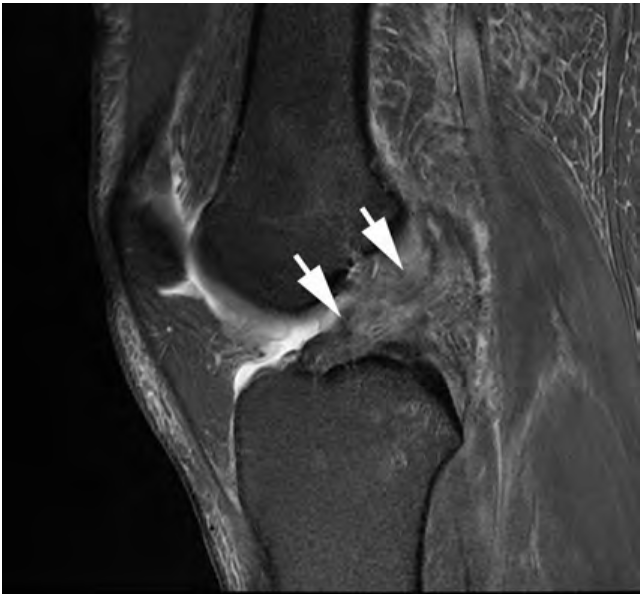

Gambar 3. Ruptur pada ACL (panah)

Tanda Primer Ruptur (Visualisasi langsung ligamen):

Diskontiunitas Serat: Adanya celah yang jelas pada ligamen. Serat-serat normal yang gelap dan tegang digantikan oleh gumpalan yang tidak teratur atau sama sekali tidak terlihat (empty notch sign).

Peningkatan Sinyal: Intensitas sinyal tinggi (terang pada sekuens T2 atau PD dengan penekanan lemak) di dalam substansi ligamen, yang mewakili edema dan perdarahan.

Orientasi Abnormal: Ligamen yang robek kehilangan tegangannya dan menjadi lebih horizontal, tampak sejajar dengan garis Blumensaat (atap interkondilar) daripada orientasinya yang normal dan lebih curam.

Tanda Sekunder Ruptur (Kerusakan kolateral):

Edema Sumsum Tulang: Pola klasik pivot shift seperti yang dijelaskan pada Tabel 2. Ini adalah tanda pendukung yang kuat.

Translasi Tibia Anterior: Pergeseran tibia ke anterior lebih dari 7 mm relatif terhadap femur, sebuah visualisasi langsung dari instabilitas.

Tanduk Posterior Meniskus Lateral yang Tidak Tertutup (Uncovered Posterior Horn of the Lateral Meniscus): Akibat pergeseran tibia ke anterior, aspek posterior meniskus lateral tidak lagi "tertutup" oleh femur.

PCL Buckling: PCL mungkin tampak memiliki kurva atau lengkungan yang berlebihan saat tibia bergeser ke depan.

Diagnosis definitif robekan ACL jarang dibuat berdasarkan satu tanda saja. Justru konvergensi bukti—sebuah tanda primer (misalnya, diskontinuitas serat) yang dikombinasikan dengan beberapa tanda sekunder (misalnya, memar tulang pivot-shift, translasi tibia anterior, meniskus lateral yang tidak tertutup)—yang memberikan kepercayaan diagnostik yang mendekati kepastian. Konsep "konstelasi temuan" ini sangat penting untuk dipahami oleh non-spesialis.

Kehadiran tanda-tanda sekunder dapat mengonfirmasi adanya robekan bahkan ketika ligamen itu sendiri tidak tervualisasi dengan baik. Selain itu, perbedaan antara robekan ACL terisolasi dan robekan ACL dengan cedera PLC penyerta bukanlah hal akademis; ini secara fundamental mengubah rencana bedah. Pemahaman ini memungkinkan dokter umum untuk menetapkan ekspektasi pasien yang sesuai dan memahami mengapa cedera ACL yang "sederhana" mungkin memerlukan rekonstruksi multi-ligamen yang lebih kompleks, yang berdampak pada waktu pemulihan dan protokol rehabilitasi.